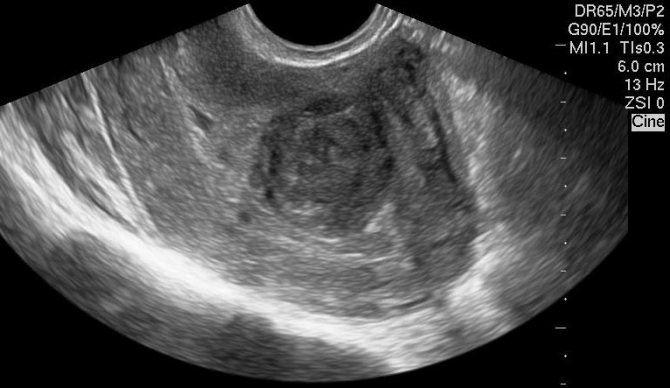

Врач-сонолог определяет миому как округлый объект с гетерогенной структурой и чёткими границами, делающими сигнал датчика слабее.

Субсерозный узел

Образование, растущее в направлении брюшины, называют субсерозным миоматозным узлом. Он не только делает контур матки бугристым, но даже меняет её положение относительно центра таза (если узел серьёзно разросся).

Опухоли яичников и субсерозные узлы

Субсерозные узлы с узким основанием нужно суметь отличит от значительной опухоли яичника, а для этого необходимо тщательное обследование, которое лучше произвести трансвагинально.

Подтверждением миомы служит выявление других узлов или кальцификатов, а также увеличенная в размерах матка.